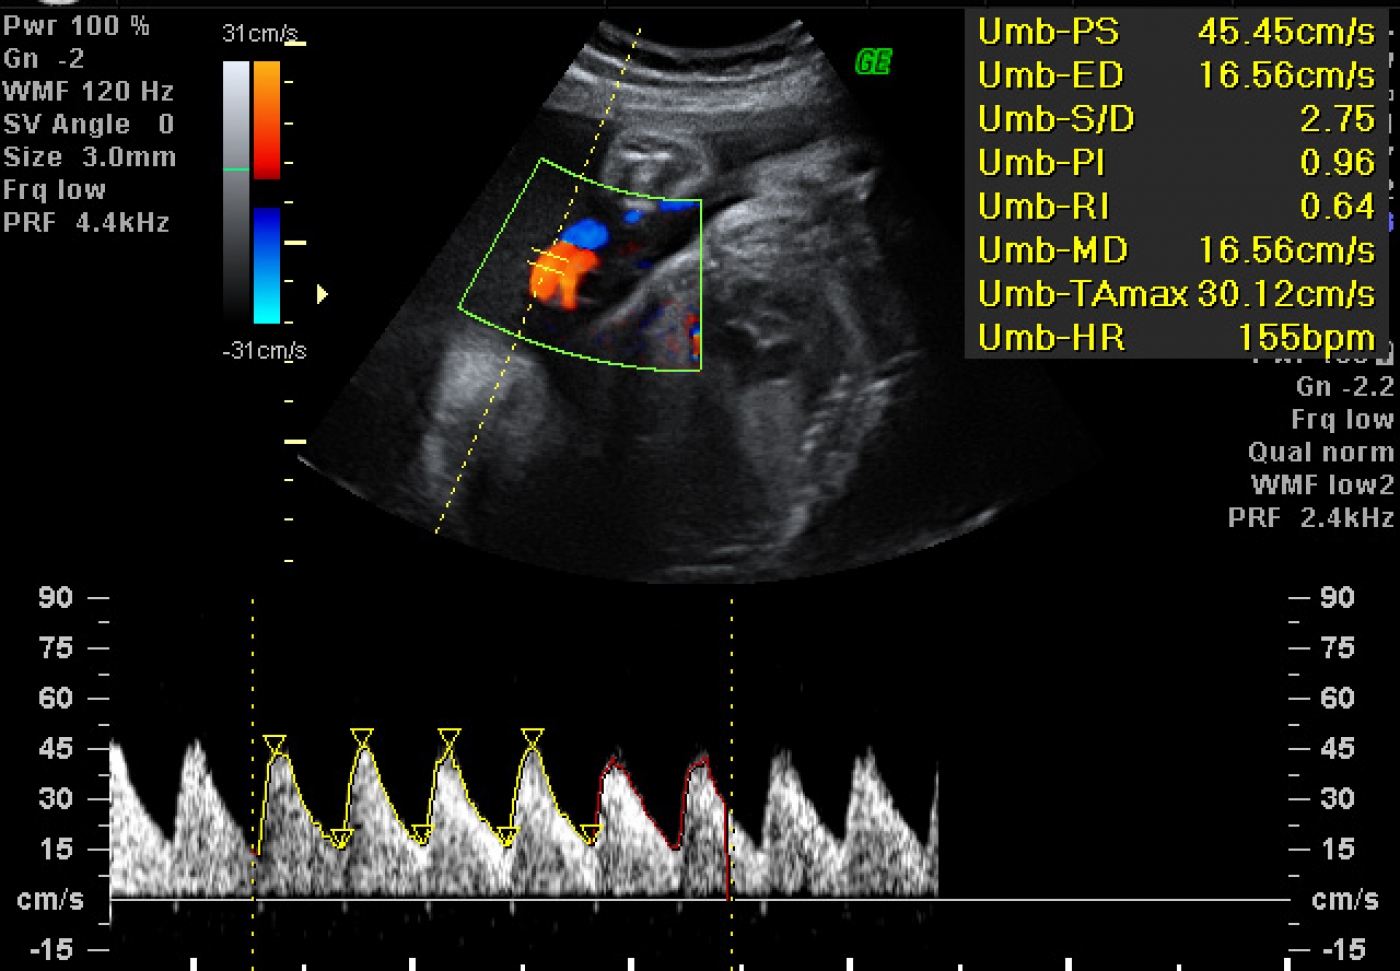

Μπορεί να αισθάνεστε έντονες καούρες και παλινδρόμηση εξαιτίας των ορμονικών αλλαγών και του ότι το έμβρυο πιέζει το στομάχι σας. Μπορείτε να δοκιμάσετε να αλλάξετε τις διατροφικές σας συνήθειες. Παραμείνετε ενυδατωμένη και αποβάλλετε το άγχος που μπορεί να έχετε ώστε να αποφύγετε τους πονοκεφάλους που είναι συχνοί την 33η εβδομάδα. Κάπου μεταξύ 32ης και 34ης εβδομάδας θα κάνετε το τρίτο και βασικό υπερηχογράφημα της κύησης, που λέγεται υπερηχογράφημα ανάπτυξης-Doppler λέγξει το αμνιακό υγρό, τον πλακούντα και τα αγγεία στου μωρού και του ομφαλίου λώρου. Έτσι, θα έχετε μερικές ακόμα φωτογραφίες για το άλμπουμ.